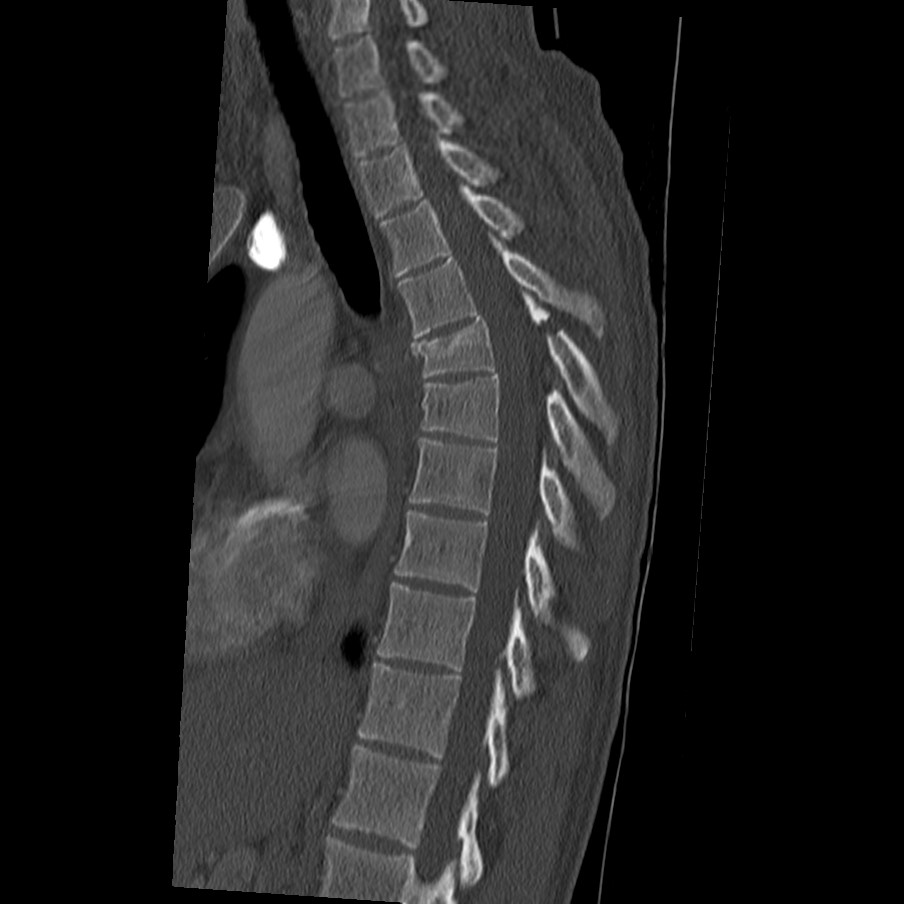

I'm currently working on a school project of medical imaging. I have an X-Ray image of a spine. The objective is to determine the dimensions (in pixels) of the smallest vertebra (based on the height of the vertebral body).". To achieve the requested objective, we must work on the image, apply some of the methods taught, improve it, and subsequently segment structures of interest.

As I understand you are mainly looking to segment regions of interest in the shared spinal X-ray image. Here is a useful discussion on segmenting CT images of spine: